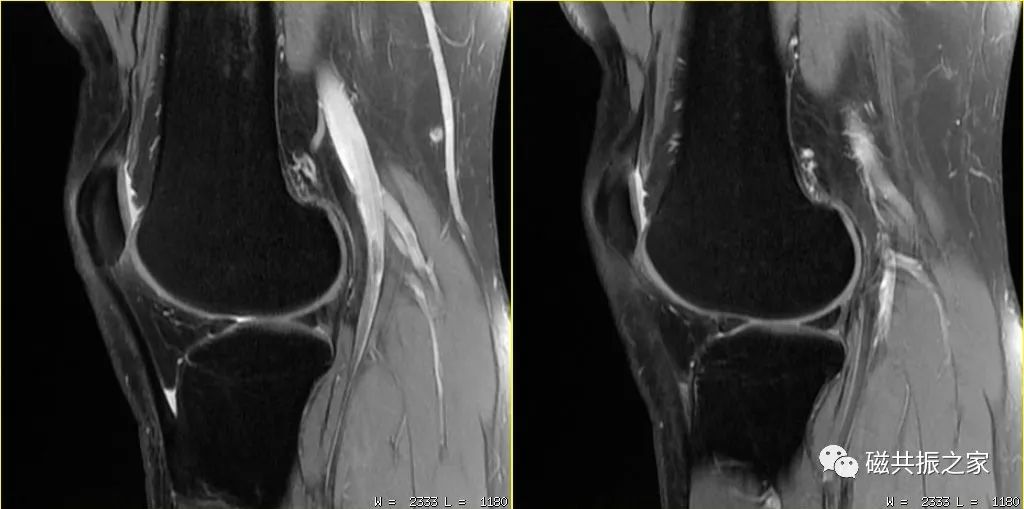

MRI的信号主要来自于水和脂肪中的氢质子,虽然较强的压脂程度可突出某些组织间的对比,但更多的脂肪被抑制掉,图像的SNR会下降,图像会更“黑”,则不利于我们做更高分辨率的图像。在进行膝关节的小体素扫描时,使用部分压脂则可以保证图像足够的信噪比。如上图的压脂程度为80%,下图的压脂为100% 。